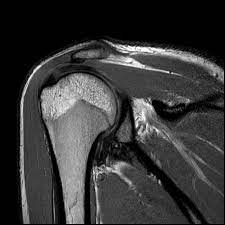

Musculoskeletal MRI is not just a diagnostic tool; it is a key to unlocking the mysteries behind chronic pain. This state-of-the-art imaging technique provides detailed visuals of bones, muscles, tendons, and ligaments, offering doctors a comprehensive view of the underlying issues that might be causing discomfort. For individuals like Priya, it is a lifeline to understanding and healing their bodies.

The process was seamless and non-invasive. As Priya lay comfortably in the MRI machine, she felt a sense of anticipation, hopeful that this was the first step toward reclaiming her life. The results were nothing short of illuminating. The MRI revealed a subtle disc herniation in her lower spine, a diagnosis that had been elusive until now. With this newfound clarity, Dr. Mehta was able to devise a targeted treatment plan, focusing on physiotherapy and lifestyle adjustments tailored to Priya's condition.

Moreover, Musculoskeletal MRI is invaluable in diagnosing a wide range of conditions, from sports injuries to degenerative diseases. It empowers healthcare professionals to make informed decisions, ensuring that treatments are precise and effective. This is particularly crucial in a country like India, where access to accurate and timely medical care can be a challenge for many.